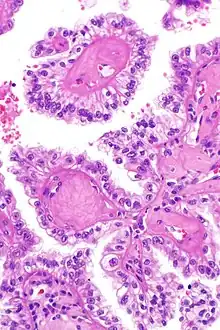

| Micrograph showing the characteristic hyalinized papillary cores found in some hereditary leiomyomatosis and renal cell carcinoma syndrome-associated renal cell carcinomas. H&E stain. | |

The renal cell carcinomas have prominent eosinophilic nucleoli surrounded by a clear halo.